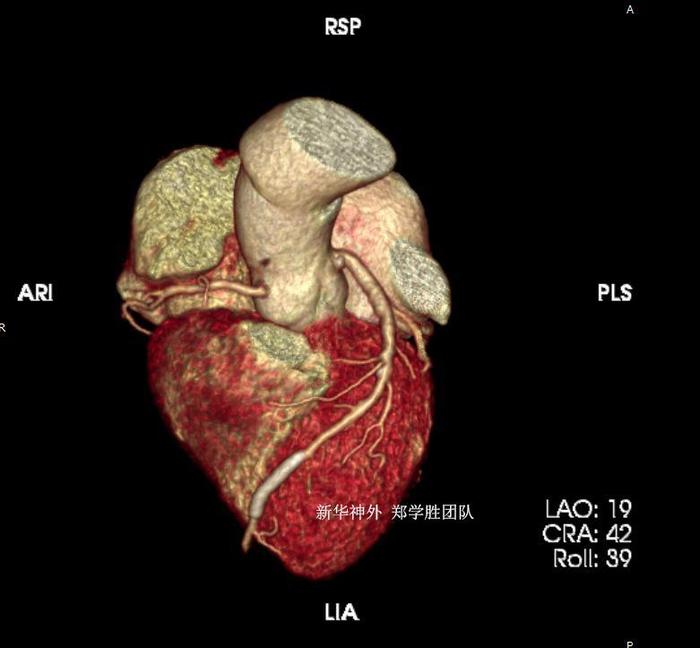

但患者有冠心病,并放过心脏冠脉支架半年,长期吃阿司匹林和波立维,有时心绞痛。手术止血比较困难,术中术后出血风险较高,术后心肌梗塞风险较高。

经过权衡以后,郑学胜团队决定予以三叉神经显微血管减压手术,围手术期予以波立维暂停5天,阿司匹林暂停3天,术中严格止血。